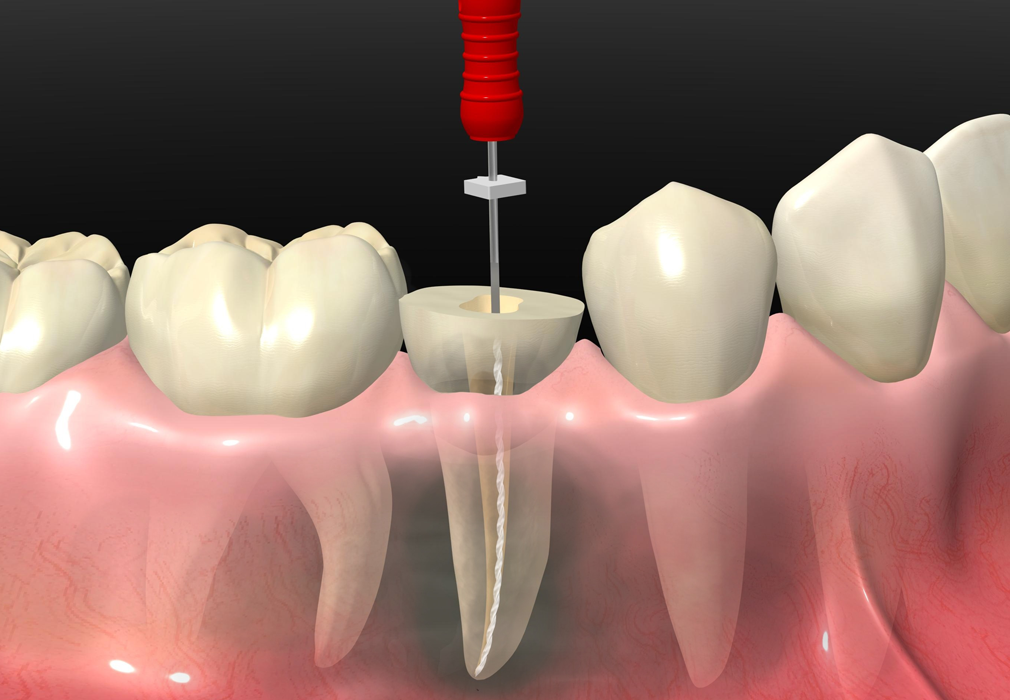

The procedure is simpler than you might think:

✔ The affected nerve is removed

✔ The canals are cleaned and disinfected

✔ They are sealed to prevent further infection